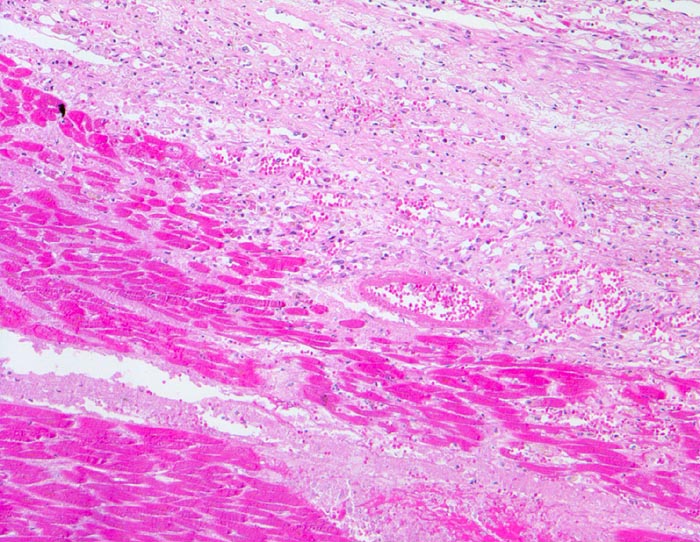

Das Präparat stammt von einer 90 jährigen Patientin. Makroskopie: schwere stenosierende Koronarsklerose mit frischem thrombotischem Verschluss des Ramus interventricularis anterior der linken Koronararterie. 8x9cm grosser akuter transmuraler anteroseptaler Myokardinfarkt.

Oben auf dem histologischen Präparat ist ein Querschnitt durch den Papillarmuskel zu sehen, unten auf dem Präparat ein tangentialer Schnitt durch die Myokardvorderwand

Papillarmuskel und Vorderwand zeigen territoriale Koagulationsnekrosen, welche vom Rand her von neutrophilen Granulozyten infiltriert werden (blauer Saum).

Ein Teil der neutrophilen Granulozyten ist bereits zerfallen (Kerntrümmer)

Das nekrotische Myokard ist erkennbar an seiner dunkleren Färbung (Hypereosinophilie) und einer Abblassung oder dem Verschwinden der Zellkerne.

Herzmuskelzellen mit Kontraktionsbandnekrosen vor allem in den Randbereichen des Infarktareals.

Die unmittelbar subendokardial gelegenen Herzmuskelzellen des Papillarmuskels sind vital (erhaltene Zellkerne), zeigen aber ein blasig vakuolisiertes und aufgehelltes Sarkoplasma (=tubuläre Degeneration) als Zeichen eines chronischen Sauerstoffmangels (sogenannte Holundermarkzellen).

Nebenbefund: Amorphe azelluläre Amyloidablagerungen in den Gefässwänden der intramyokardialen Arterien. (Senile kardiovaskuläre Amyloidose).